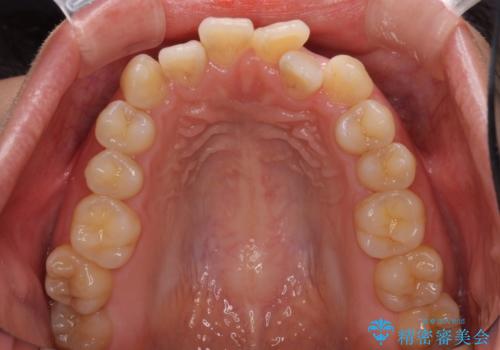

前歯のデコボコを治したい ワイヤー矯正

- 前歯のデコボコが気になるとのことで来院された患者様です。

目立たない装置と金属のワイヤーで矯正治療を行うこととしました。

1年半程度の期間を見込んでいましたが、上下の真ん中の位置をできる限り合わせるための調整に少し時間がかかってしまいました。

咬み合わせが安定し、前歯の汚れも付きにくくなりました。